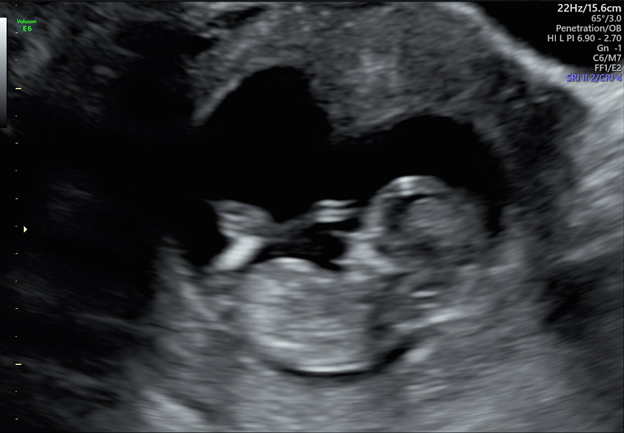

12 weeks: We had our third ultrasound and doctors visit today. At this visit they measured the nuchal thickness of the fetus along with my blood work for risk of down syndrome, trisomy 18 & 13, and other chromosomal abnormalities. All (THANKFULLY) came back within normal ranges. My doctor found that I had also lost two pounds since my last visit and put me one two medications to help with the morning sickness. Let me just tell you those are miracle drugs. I feel like a new person!